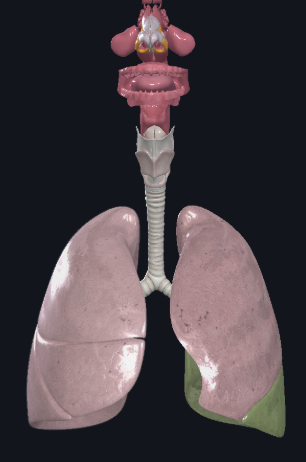

What structure is this?

Superior Lobe of the right lung

What structure is this?

Middle lobe of the right lung

What structure is this?

Inferior lobe of the right lung

What structure is this?

Right lung